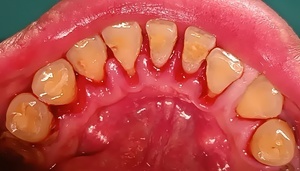

After(歯石除去後)

歯石が除去され、歯の表面が露出しました。歯間も開き、歯間の隙間が見えるようになりました。治療結果には個人差があります。